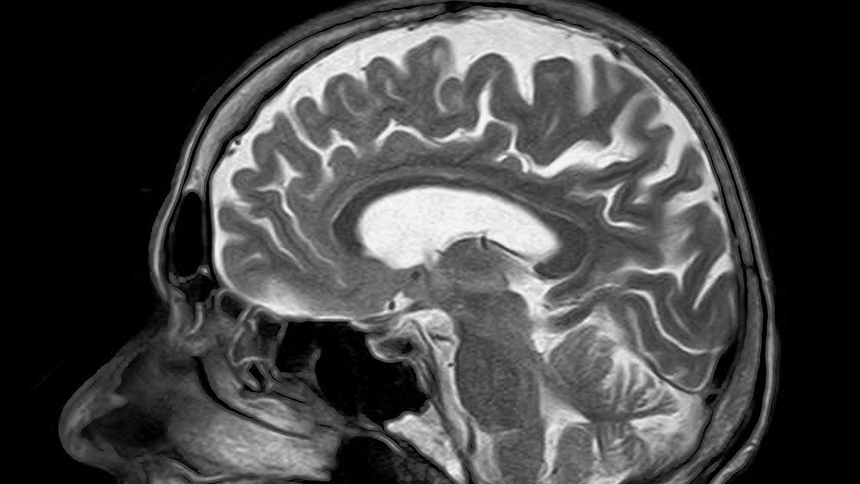

研究人員分析了1293名參與者的大腦灰質掃描圖和1119名參與者的大腦白質掃描圖,尋找它們在發育過程中的變化,如皮質和皮層下腦區灰質的厚度、體積和表面積以及腦區白質特徵。

結果顯示:在幼年期和青春期早期,雙語者的大腦相比於單語者呈現更多的灰質,而在青春期中後期,雙語者的大腦白質的完整性也增加了。該發現不僅證實了雙語大腦結構和單語大腦結構可能不同的說法,還表明,這種不同的大腦發展可能會對人的生命以及生命活動產生影響。

灰質是一種神經組織,是中樞神經系統的重要組成部分,由大量的神經元胞體及其樹突聚集在一起形成。中樞神經系統的另一個重要組成部分是白質。

所以,灰質和白質的增加會使大腦變得更高效。